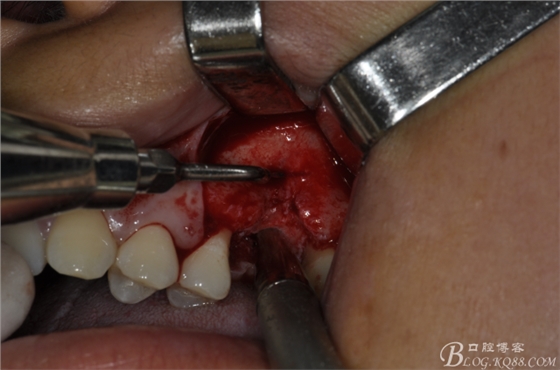

術(shù)中照片。

超聲骨刀切開骨外板 上頜竇外提一例